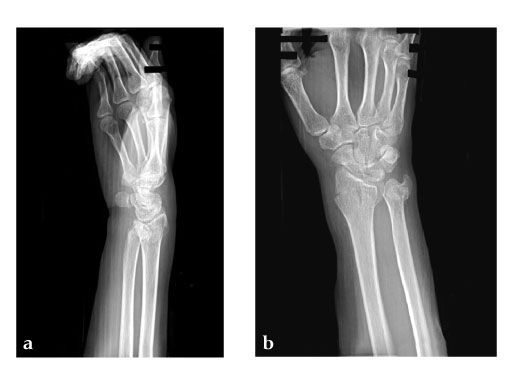

28-year-old woman.

Fig 1ab: X-rays preoperative.

Fig 3ab: X-rays postoperative.